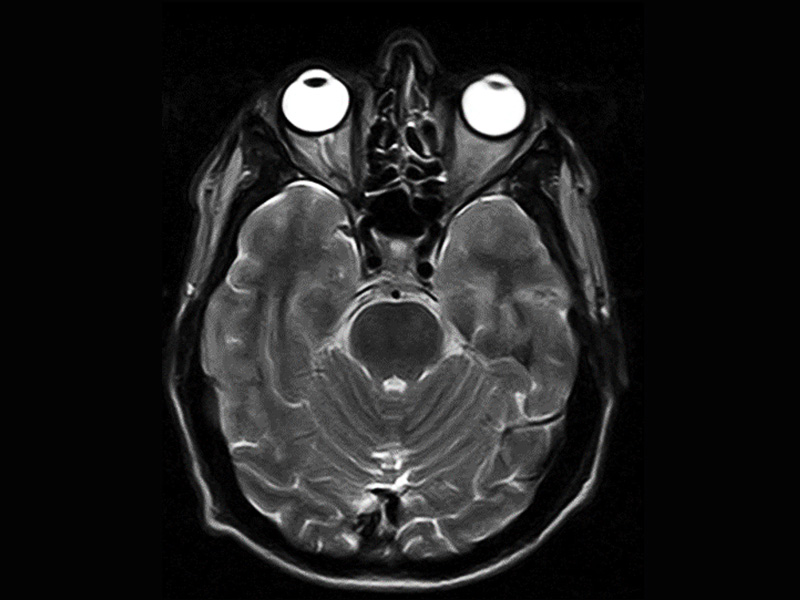

Klinické snímky